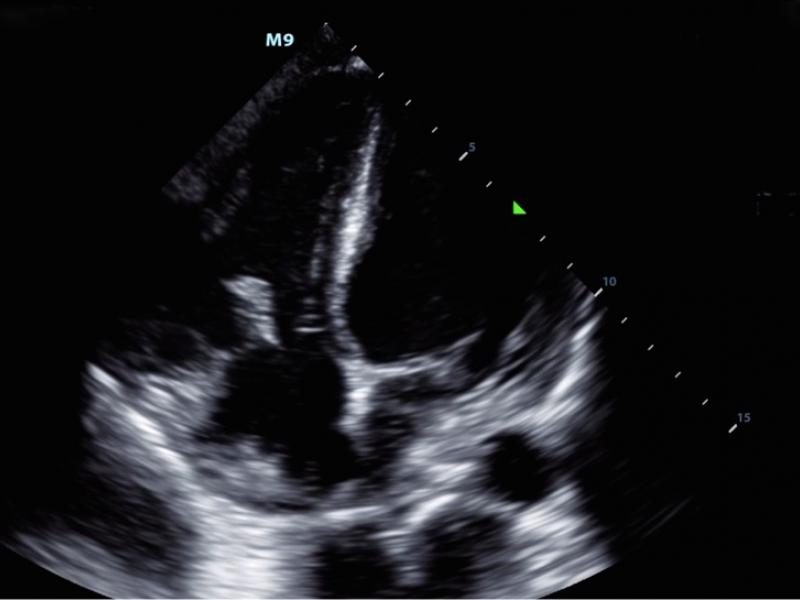

30-year-old male with no significant past medical history

What's the Diagnosis?  By Dr. Michael Tom

A 23 year old male with a history of IVDU presented with